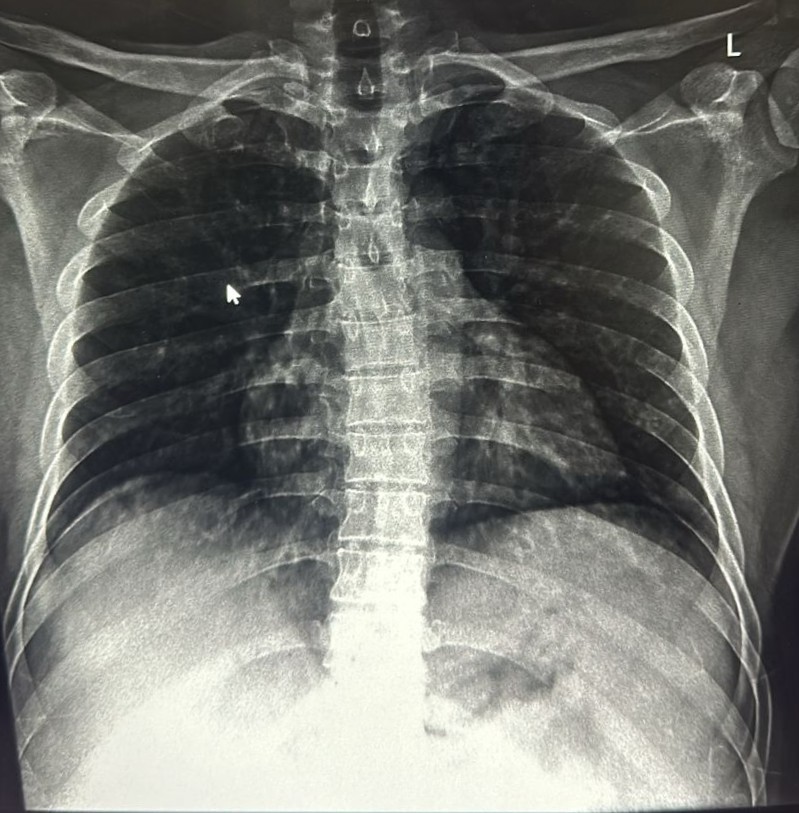

| 205 | IGGMC, Nagpur, Nagpur | P2 | 29-4267 | MOHAMMAD HANIF SUREYYA | Consent taken on Paper | 55 Yrs. |

Provisional Diag : PTB?

Final Diag : PNAEMOTHORAX /CLINICALLY DIAGNOSED PTB |

TB Case (Confirmed) | LEFT SIDED PNAEMOTHORAX | Abnormality visible on x-ray |